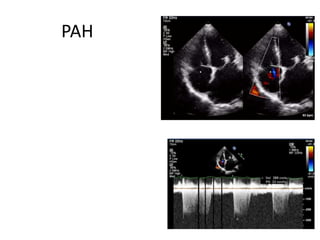

PAH

• TR ,tricuspid annulus

• Secondary pulmonary HTN-TR

PASP (mmHg) <30 30-50 >50